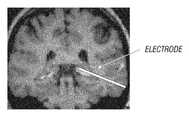

FIG. 3 illustrates example placement of a single stimulation lead and stimulation electrode in communication with the amygdalohippocampal complex;

FIG. 3 illustrates example placement of a single stimulation lead for electrical stimulation of the amygdalohippocampal complex by a stimulation electrode. Placement of the stimulation electrode is visualized by x-ray monitoring or other visualization means during implantation. The brain region to be stimulated is predetermined before implantation using such medical imaging tools as magnetic resonance imaging, computerized axial tomography, and positron emission tomography. Multiple stimulation leads and electrodes are used in other embodiments of the invention. It is understood by one of ordinary skill in the art that brain regions are not well defined and that individual variations make exact placement of the stimulation electrode vary according to the patient's anatomy and pathology. Certain embodiments of the invention contemplate a stimulation electrode in communication with the amygdalohippocampal complex and the illustration inFIG. 3 is an approximation of the predetermined placement for the patient imaged.